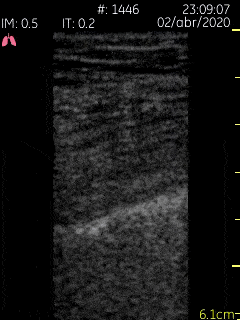

This lung ultrasound clip demonstrates multiple scattered b lines emanating from an irregular pleural line in a patient with known COVID-19. Image courtesy of Dr. Jaime Alejandro Sánchez Gutiérrez (@pleuralpocus)